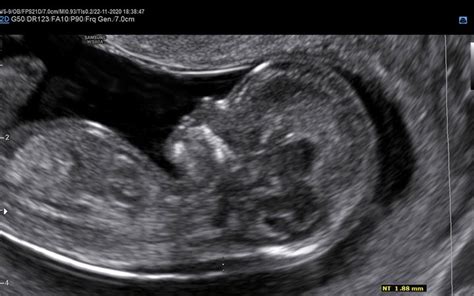

Ultrazvočno merjenje nuhalne svetline pri plodu je sodobna neinvazivna preiskava, ki v kombinaciji s krvno preiskavo (dvojni hormonski test ali DHT) služi kot presejalni test za izračun tveganja za rojstvo otroka z Downovim sindromom (kromosomsko napako s tremi kromosomi na 21. paru). Nuhalna svetlina je namreč tanek sloj tekočine pod kožo na vratu ploda. Povečana količina te tekočine je lahko znak, da plod razvija določeno kromosomsko nepravilnost, kot je Downov sindrom, Edwards sindrom ali Patau sindrom.

Ultrazvočno merjenje nuhalne svetline mora biti opravljeno med 11. tednom 0 dnevi (dolžina ploda 45 mm) in 13. tednom 6 dnevi (dolžina ploda 84 mm) nosečnosti. Pregled praviloma opravimo preko trebuha nosečnice - transabdominalni ultrazvok. Le redkokdaj je potreben pregled skozi nožnico - transvaginalni ultrazvok. Nosečnico prosimo, da pred pregledom popolnoma izprazni sečni mehur. Za natančno merjenje nuhalne svetline je pomembno, da je plod v pravi legi. Zato pregled lahko traja različno dolgo.

Med samim pregledom plodu izmerimo frekvenco srca, njegovo velikost od vrha glavice do trtice (Crown-Rump Length - CRL), premer glavice. Preverimo prisotnost nosne kosti, ocenimo obliko glavice in možganskih struktur. Poiščemo srce, želodček in mehur ter preverimo, ali je trebušček v celoti prekrit s kožo. Preštejemo dolge kosti na zgornjih in spodnjih udih ter pregledamo hrbtenico. V določenih primerih lahko z manjšo stopnjo gotovosti (okoli 60 %) napovemo spol otroka.